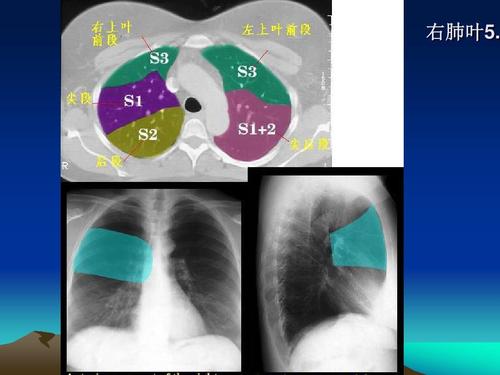

ct肺分叶分段解剖图,肺的分段分叶解剖图ct

ct肺的分叶分段

文档网 所有分类 医药卫生 临床医学 ct正常彩色解剖图-肺段 肺ct正常

胸部ct肺段划分口诀

肺部分段解剖